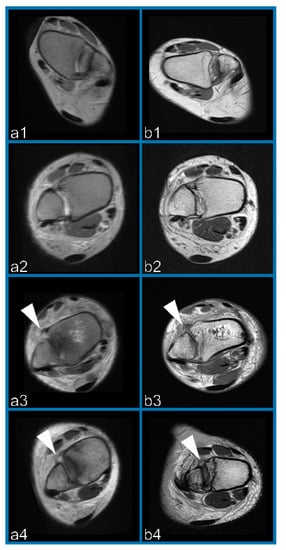

2.4. Reconstruction of Oblique-Fusion Reconstruction Images

2.5. Experimental Setup